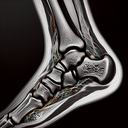

МРТ гомілково-ступневогу суглобу

Магнітно-резонансна томографія (МРТ) гомілково-ступневого суглоба — це сучасний метод діагностики, що дозволяє отримати детальні зображення тканин. Ось кілька ключових моментів про цю процедуру: 1. **Точність**: МРТ забезпечує високоякісні зображення зв’язок, сухожиль, хрящів та кісткових структур...